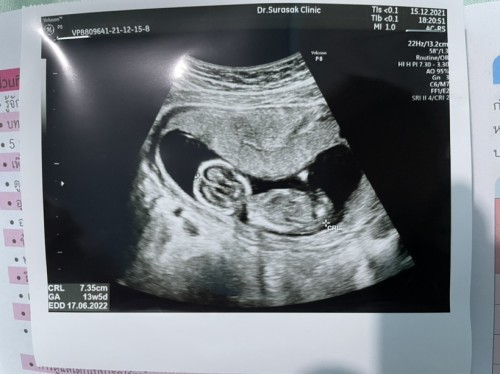

ซาว 13wค่ะเมื่อวันที่ 2\12 ลุงหมอบอกน่าจะผช.วันที่30นี้ไปหาหมออีกรอบ น่าจะ100%กับเพศค่ะ